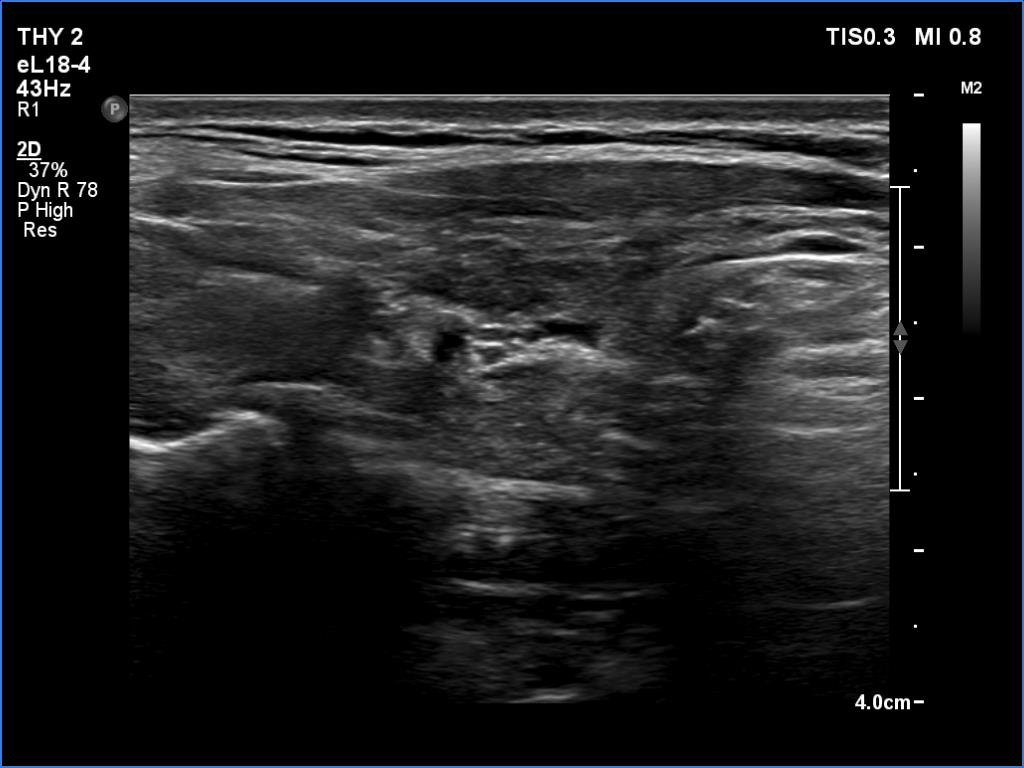

Ultrasonography. The thyroid was atrophic and deeply hypoechoic. The dimensions were 8x9x18 and 10x7x21 mm (width x depth x length), right and left lobe, respectively.